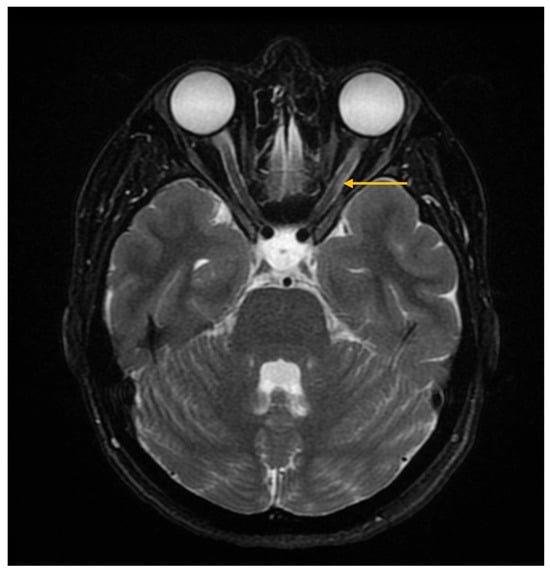

The Role of Imaging Techniques in the Evaluation of Extraglandular Manifestations in Patients with Sjögren’s Syndrome

Sjögren’s syndrome is a chronic autoimmune disease marked by lymphocytic infiltration of the exocrine glands and the development of sicca symptoms, yet some patients also develop extraglandular involvement. Imaging has become relevant for describing these systemic features and supporting clinical assessment. This review discusses the roles of ultrasonography, elastography, computed tomography, and magnetic resonance imaging in evaluating multisystem disease associated with Sjögren’s syndrome. Ultrasonography and elastography help assess muscular involvement by showing changes in echogenicity and stiffness that reflect inflammation and later tissue remodeling. In joints, ultrasound can detect synovitis, tenosynovitis, and early erosive changes, including abnormalities not yet evident on examination. Pulmonary disease, most often with interstitial lung involvement, is best evaluated with high-resolution computed tomography, which remains the most reliable imaging modality for distinguishing interstitial patterns. Magnetic resonance imaging is valuable in assessing neurological complications. It can reveal ischemic and demyelinating lesions, neuromyelitis optica spectrum features, or pseudotumoral appearances. Imaging is also essential for detecting lymphoproliferative complications, for which ultrasound and magnetic resonance imaging can reveal characteristic structural and diffusion-weighted imaging findings. When combined with clinical and laboratory information, these imaging methods improve early recognition of systemic involvement and support accurate monitoring of disease progression in Sjögren’s syndrome. Full article